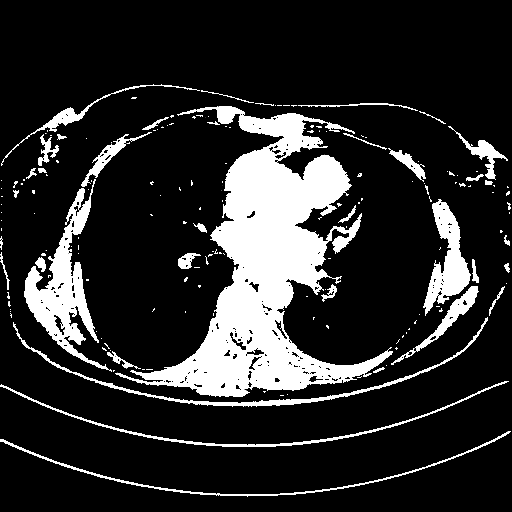

Generated VENOUS CT scan (A→B translation)

Full window (WL 1023.5, WW 4095 β†’ Low βˆ’1024, High +3071)

Actual HU range: [-1024.0, 3071.0]